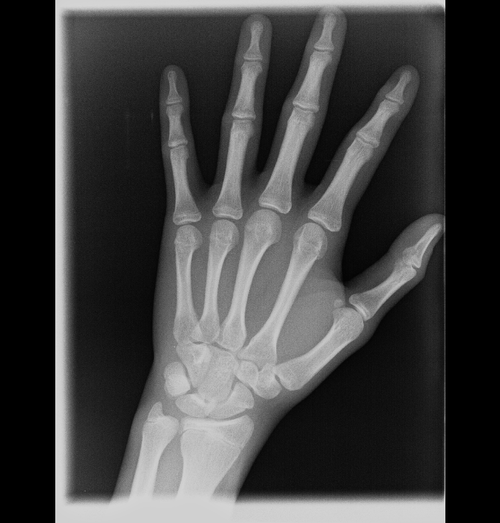

Am I reaching 5’7+? I’m currently 5’5 and 17 last time I measured and have around 5’8 wingspan my dad 6’0 mom 5’3 moms side is on the shorter side but dads side is more on the taller side they’re all above average 5’9 minimum I’m more of a late bloomer and recently have started growing tiny bit of armpit hair and just a tiny bit of chin hairs like (5-10 hairs) also important I prob haven’t grown in about a year

The x ray shows my hand is closing but I heard that knee growth plates close later

Hand doesn't even look close to closing you're probably fine for now, but I would still start using pharmaceuticals

U fr? If I look at indicators on google it looks pretty close to me

Yours still has a very obvious gap indicating some growth left, which is why I said I would start using pharmaceuticals if I were you to maximise that.